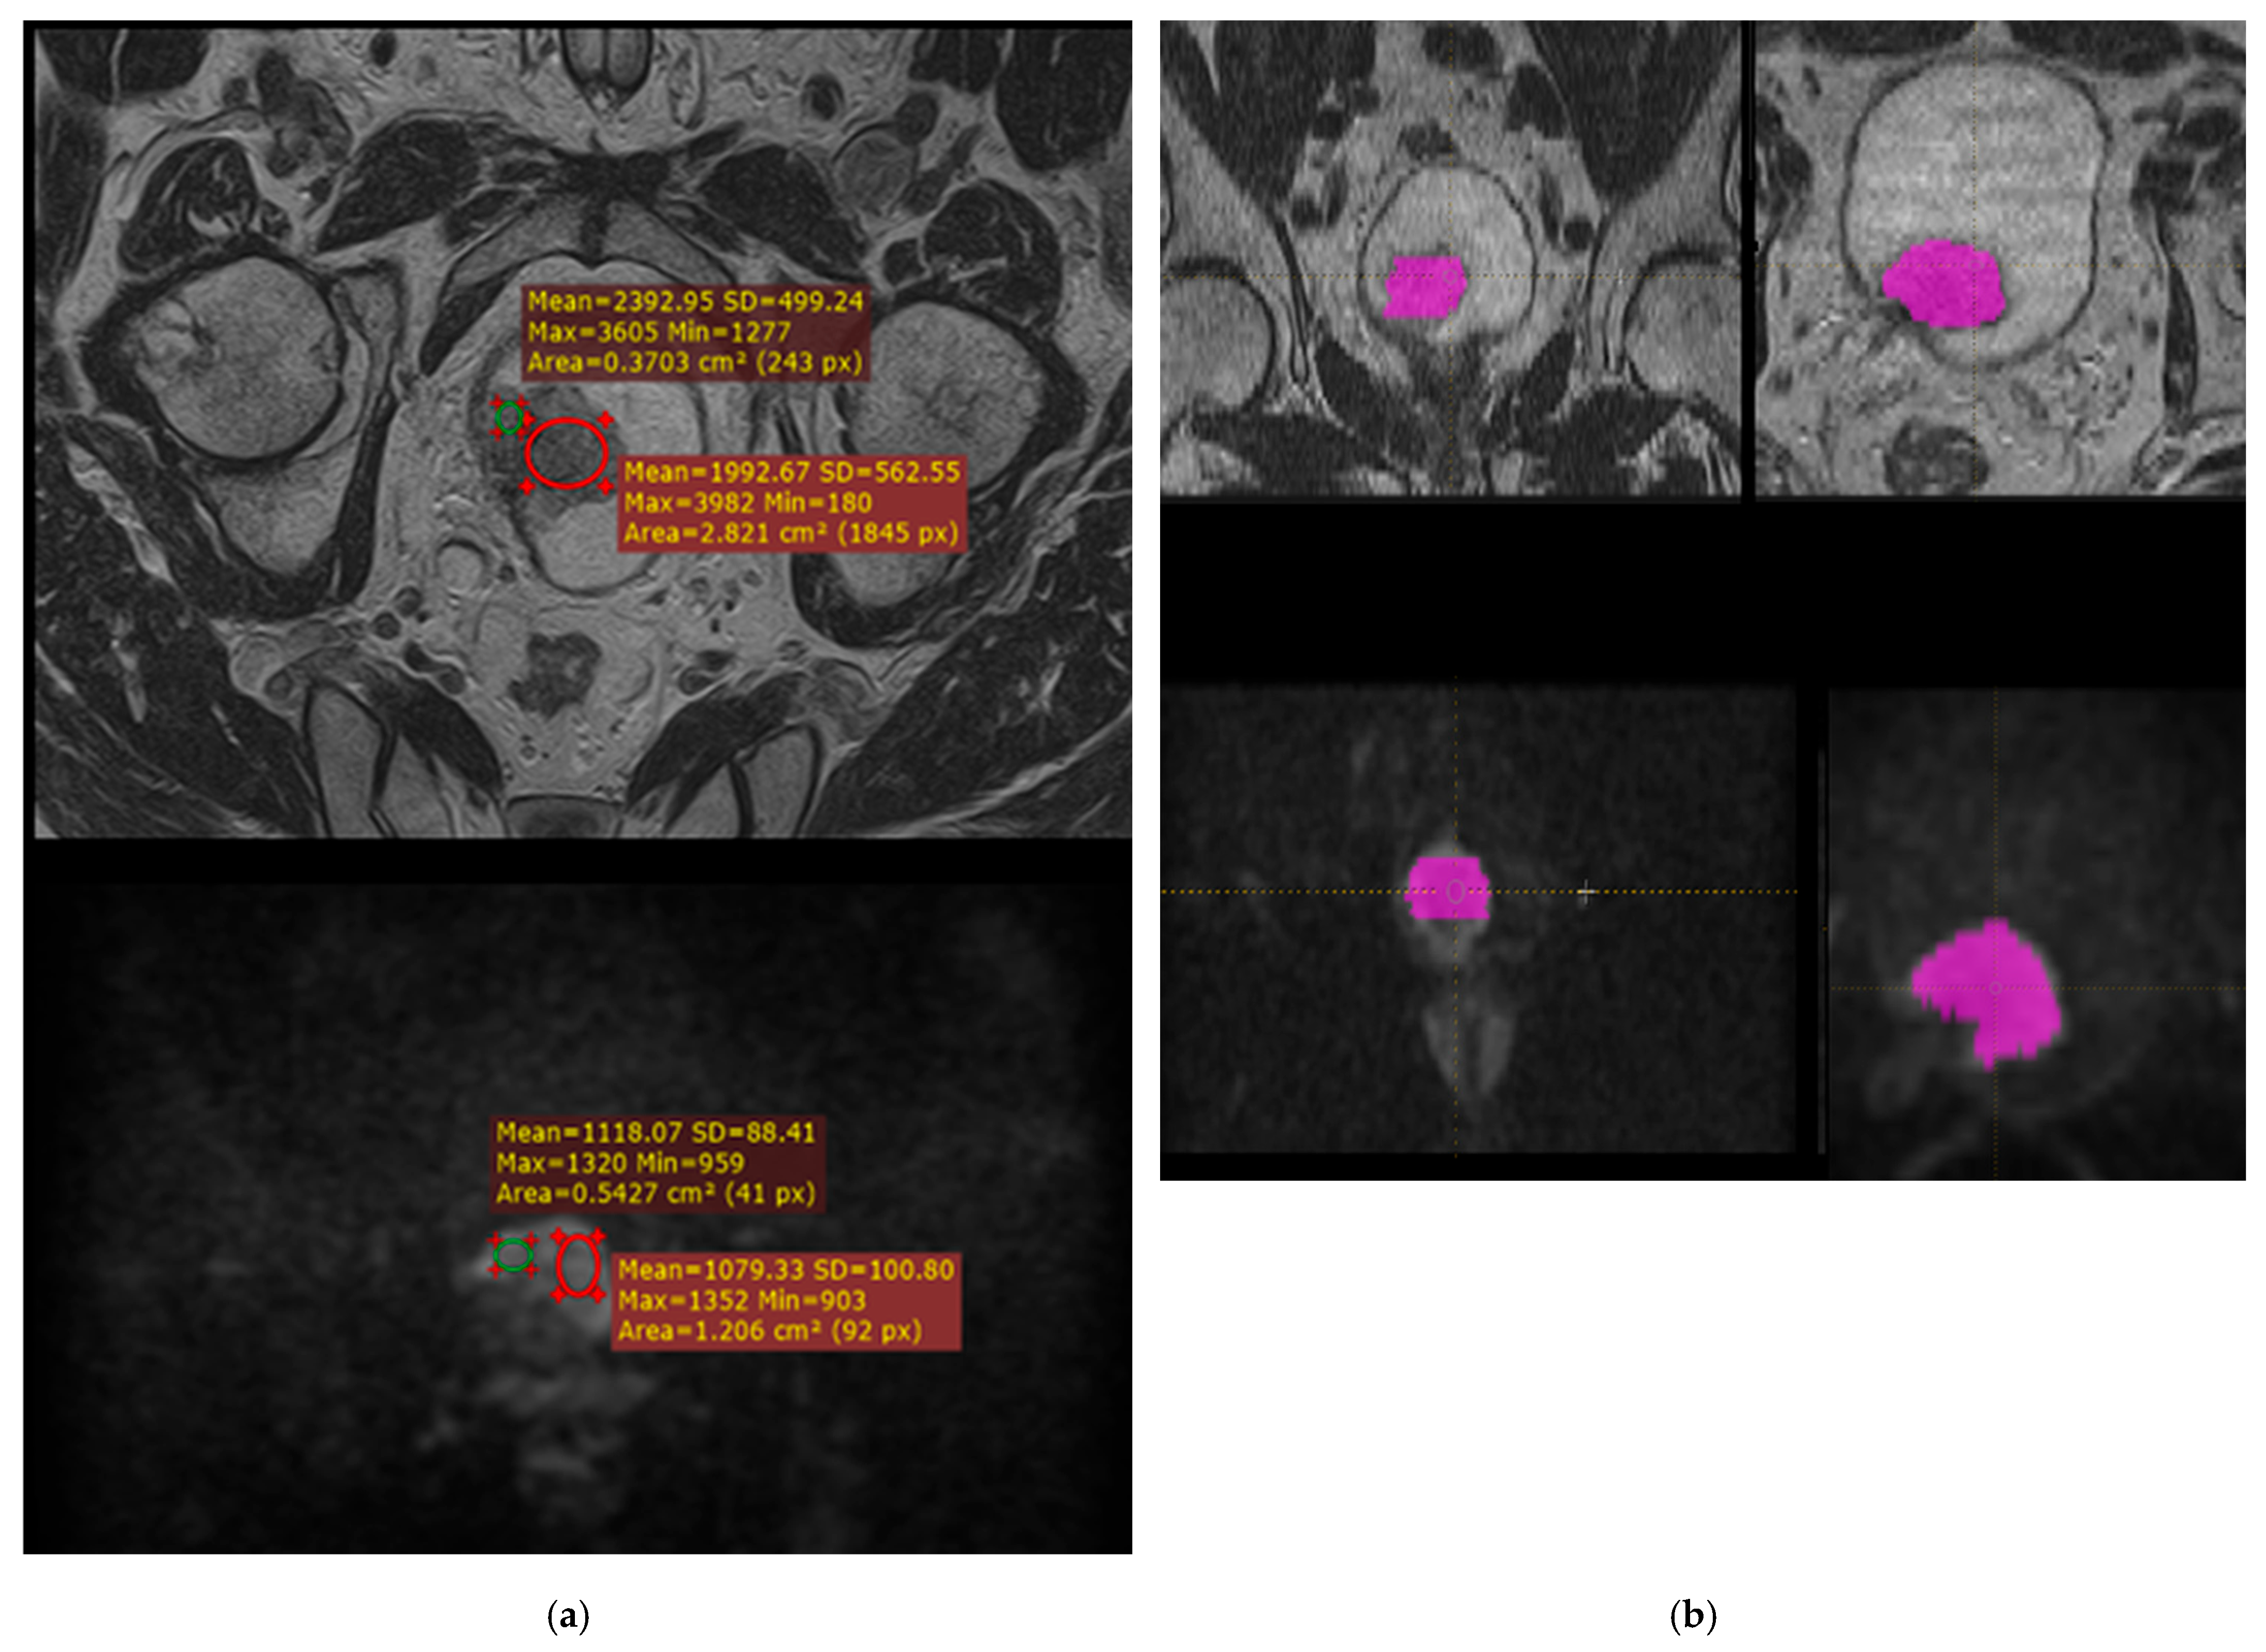

2.4. ROI Extraction

2.5. Feature Extraction